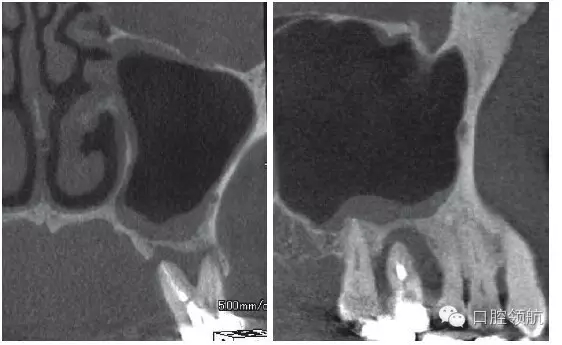

患者,78歲,男性 ,因6 牙齦腫脹來院,檢查見牙根周圍因牙槽骨缺損表現(xiàn)為透過影像(圖1)。在制訂治療計劃時,對于因重度牙周炎、慢性根尖周炎、牙根折斷等原因?qū)е碌难例X缺失需要行上頜竇底提升術(shù)的病例,不能單純考慮缺牙區(qū),要同時考慮鄰牙狀態(tài),并用CBCT確認(rèn)上頜竇底黏膜是否有增厚,這是非常重要的。該病例,根據(jù)CBCT能夠觀察到上頜竇底黏膜增厚,拔牙即刻植入感染幾率較高。計劃拔牙后4~8周,拔牙窩牙齦上皮愈合但拔牙窩未消失時(拔牙后早期植入)植入種植體(圖2)。

圖1 CBCT影像確認(rèn)是由6 引起的上頜竇底黏膜增厚。